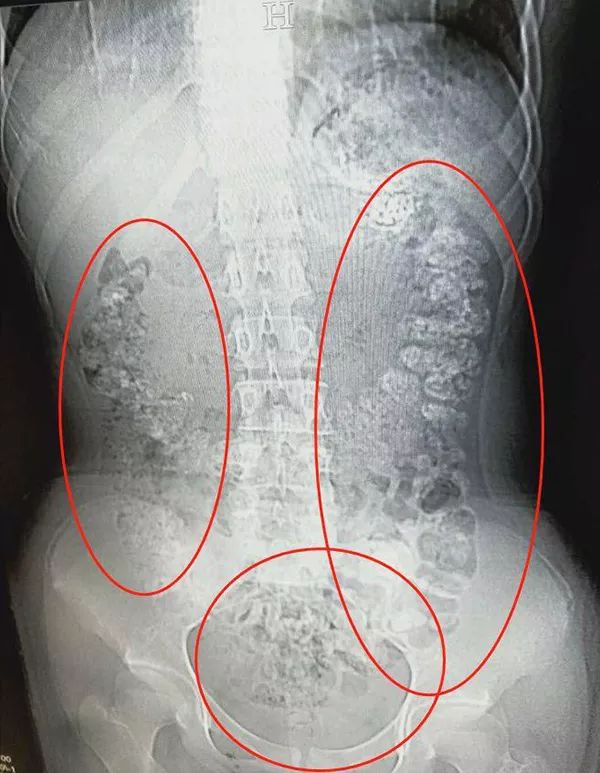

CT检查发现胃肠道

布满一颗颗圆圆的高密度阴影

——没有消化的“珍珠”

接诊医生张楼炜见她肚子鼓鼓的,便安排了腹部CT,检查结果让他一惊:患者胃部、横结肠、升结肠、降结肠、乙状结肠,一直到肛门,全是颗粒状阴影,足有百余颗。